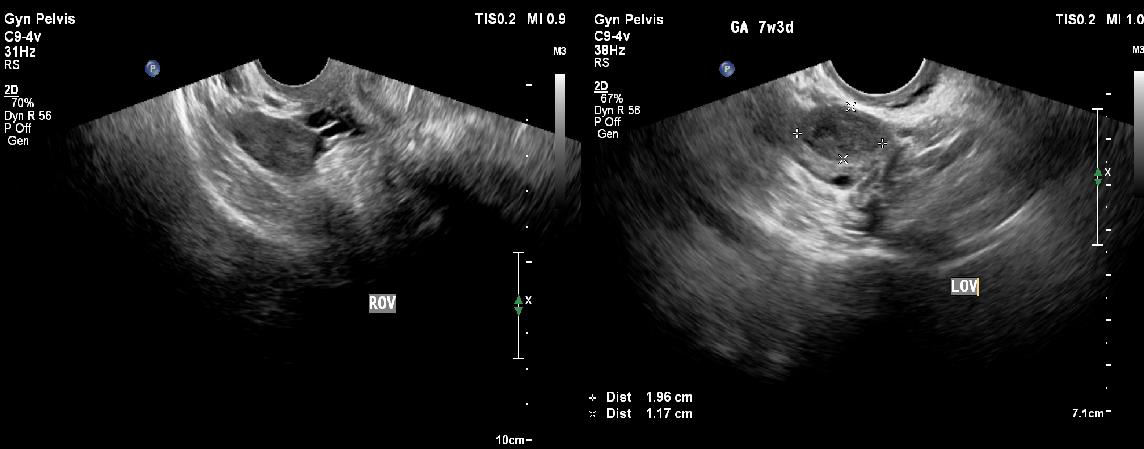

These gestational sacs were seen separate from but adjacent to the

left ovary, confirming a tubal origin.

The left ovary showed the presence of a corpus luteum measuring 1.9 x 1.1 cm in size [Figure 4b].

The right ovary and fallopian tube were normal [Figure 4a]. Transvaginal ultrasound also confirmed the absence of an intrauterine gestational sac, thus ruling out a heterotopic pregnancy. Incidentally, a subserosal seedling fibroid was noted in the anterior uterine wall. No free fluid/hemoperitoneum was noted in the abdomen or pelvis at the time of ultrasound.